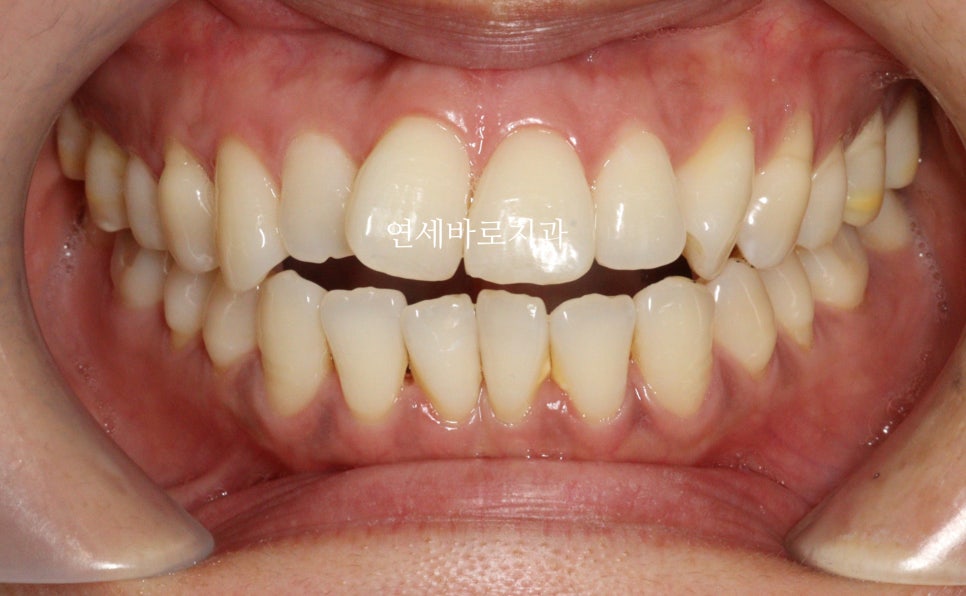

초진 시 상태

처음 내원하셨을때 사진입니다.